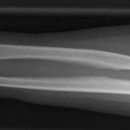

Unterarm total seitlich (2. Ebene radio-ulnaris)

Technik

• FDA: 1,05m

• Ausgangsformat: 20/43

• Übertischaufnahme

Indikation

Fraktur, Stellungskontrolle, Osteosynthesematerial

Anmerkung

Radius und Ulnar müssen sich weitgehend decken. Dies ist aber nur möglich, wenn man den Unterarm so einstellt wie HG seitlich.

Qualitätskriterien

Anmerkung zur Qualitätskriterien umändern. Und dazu: dargestellte Nachbargelenke sollen rein seitlich abgebildet sein.